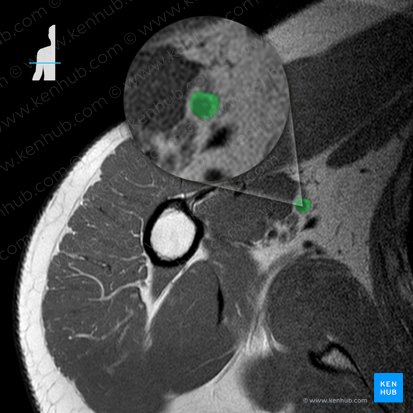

Arteria brachialis

Verlauf

Gleich nach dem Austritt aus der Axilla gibt die A. brachialis ihren ersten Ast ab, die A. profunda brachii. Anschließend verläuft sie weiter im Sulcus bicipitalis medialis, die durch den M. biceps brachii, M. triceps brachii und Septum intermusculare mediale gebildet wird, zur Ellenbeuge. In dieser Rinne wird sie vom Gefäß-Nerven-Strang des Armes (u.a. dem N. medianus, N. ulnaris und Vv. brachiales) begleitet. Auf dem M. brachialis liegend zieht sie weiter nach distal und teilt sie sich in der Ellenbeuge in ihre Endäste auf: die A. radialis und die A. ulnaris.